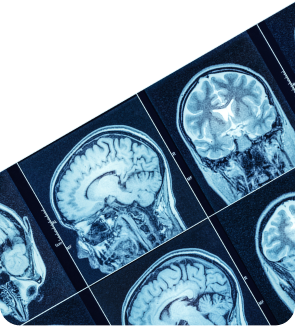

Что такое МРТ?

• Магнитно-резонансная томография — это аппаратный метод диагностики: томограф послойно сканирует органы и ткани организма. МРТ безопасна, так как не создаёт лучевой нагрузки.

МРТ лучше визуализирует мягкие ткани (а КТ — костные структуры). С помощью МРТ исследуют головной и спинной мозг, суставы, сосуды, органы малого таза и многое другое.

Аппараты с напряжённостью магнитного поля 1,5 Тесла — это высокопольные томографы. Они выполняют изображения со срезом толщиной от 1 мм, что позволяет заметить даже малейшие отклонения от нормы.